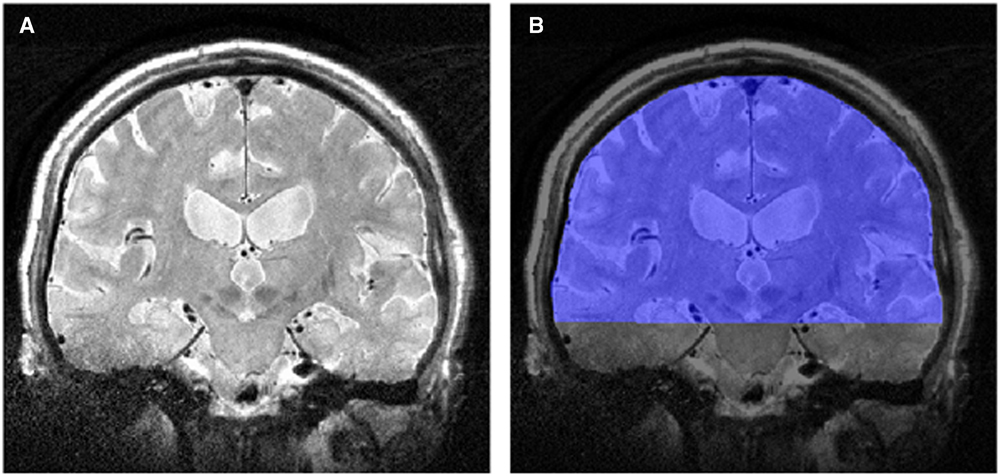

Images were down-sampled to 1×1, 2×2, 3×3, and 4×4 mm2 in-plane spatial resolutions using the bicubic interpolation algorithm in ImageJ (http://rsbweb.nih.gov/ij/). Non-uniform image intensity was corrected using bias-field correction in SPM8 (http://www.fil.ion.ucl.ac.uk/spm). The single coronal slice that maximally included the precentral gyrus and the CST, including the internal capsule, was selected for each subject under the supervision of a neurologist; this slice was masked by manually drawing an region of interest (ROI) from the cortex to the peduncles using ITK-SNAP (http://www.itksnap.org). The ROI included gray and white matter (GM and WM) (Figure 1). This anatomical region was selected for TA to (a) include maximally affected structures in ALS and (b) exclude the skull. The mean pixel intensity was calculated from the histogram of the ROI from patients and controls to ensure the absence of image intensity differences that may affect the extracted texture features.

Figure 1 (A) T2-weighted image in the coronal plane, and (B) the region of interest (in blue) for the texture analysis.